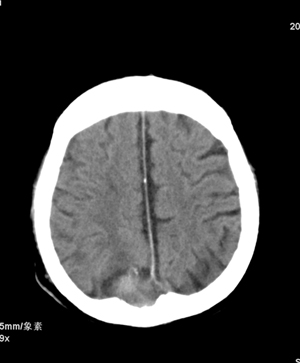

标题: CT13600:男,70,头晕思睡7天,BP160/100MMHG,颅N(-) [打印本页]

标题: CT13600:男,70,头晕思睡7天,BP160/100MMHG,颅N(-)

肢体活动肌力均正常。临床印象:脑血管病变。ct意见:脑软化灶,腔梗,请看看枕部病变是脑膜瘤,血管畸形还是其它

1.右基底节区脑软化灶。

2.右顶后部病变,脑膜瘤可能性大。

建议:强化扫描。

枕骨骨质吸收破坏,局部病灶密度不均,周围见低密度水肿带,考虑脑膜瘤,建议增强扫描。

建议:强化扫描。不除外静脉窦血栓形成